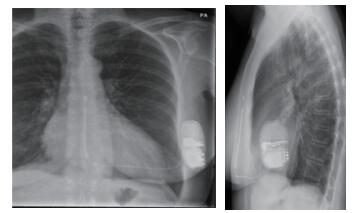

1 资料与方法患者女性,56岁,因长QT综合征植入S-ICD 1.5年。既往因“心脏瓣膜病”于2016年4月19日行二尖瓣、三尖瓣位机械瓣膜置换术,术后常规抗凝,维持INR值为2~3。术后6个月由于长QT综合征导致的反复室颤,考虑到经静脉植入ICD卡瓣等问题,选择植入S-ICD,常规S-ICD ECG筛选通过后,于2016年11月29日植入一台S-ICD(图 1)。术后继续华法林抗凝治疗,患者在2018年5月28日07:41睡觉的过程中接受到了两次电击,遂来医院就诊,复查电解质未见异常; 心电图无室性心动过速和室早事件; 患者电击前无明显不适症状,放电后亦无栓塞表现。联系ICD厂家工程师,于当日20:42使用S-ICD程控仪对患者植入的S-ICD进行问询,测试电池、阻抗都在正常范围内(阻抗55 Ω, 直接测量所得)。设备记录到了两次事件(图 2),分析两次放电事件的EGM,S-ICD感知向量为出院前自动优化的Primary向量(增益为1),这个向量所记录到R波幅值较低(图 3)。当发生短阵的房颤事件,f波都被误感知为R波,因为频率较快,标记为“T”(快室性心律失常事件),满足18/24诊断标准后开始充电,充电后确认快心室率事件仍然存在后放电,放电终止了房颤。

| 图 1 患者植入S-ICD后胸片 |